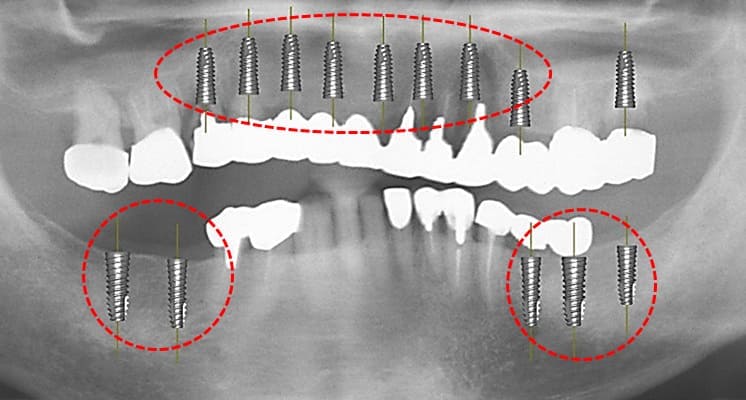

上顎前歯部と小臼歯部の温存不可能な残根を抜歯して1か月ほど待機して歯肉が抜歯窩を完全に閉鎖した状態でCTと口腔内の印象を取り最終補綴の予想WAX UPを1行いサージカルガイドを作成した。その後、上顎にインプラント8本を埋入した。

上顎にインプラント8本を埋入した術後のパノラマXP所見:上顎骨に対するインプラントの長さに関しては12mm-10mmが適切であり前歯部では12mmを小臼歯部では10mmを選択している。また左下のブリッジに関しては温存できなかった第2大臼歯が抜去されている。

上顎のインプラント埋入後約1か月で、両側下顎臼歯部にインプラント埋入を行った。左下のインプラント埋入では小規模の骨増生を伴うインプラント埋入を行った。

両側下顎臼歯部に対してのインプラントについては8mmから10mmが選択されるが骨量が十分あったことから10mmを選択して埋入した。左側の小臼歯部では水平的骨が若干、不足しているためドリリング時に採取された自家骨を骨増生として利用した。